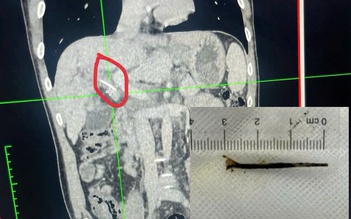

Hóc xương cá dài 3 cm xuyên vào đường mật... tưởng bị ung thư

Bệnh nhân bị áp xe nặng do mảnh xương gà cắm sâu thực quản

Áp xe ruột do thanh nứa nhỏ ghim trong ổ bụng